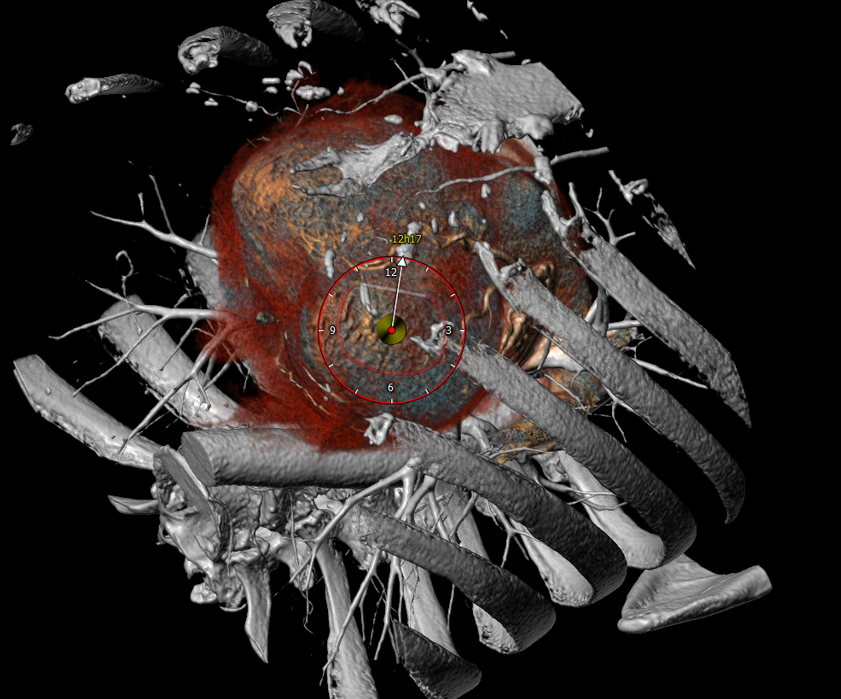

经华西医院心外科MDT团队综合评估,该患者为老年重度FMR患者,考虑外科瓣膜置换手术风险极高,决定进行MitraFix®经心尖二尖瓣植入。术前心脏CTA瓣环面积折算最大直径37 mm 模拟植入34号二尖瓣瓣膜, 收缩末心室Neo LVOT面积约230mm²。

术前瓣环形态评估

术前心尖入路评估

手术采用左侧第六肋间微创5cm切口心尖入路,在超声引导下,清晰识别MitraFix®输送系统准确跨瓣,并将人工瓣膜准确释放于二尖瓣瓣环,瓣膜释放后支架贴合牢固,术后无反流,二尖瓣前向血流通畅、跨瓣压差3mmHg,左心室流出道通畅,流出道血流速度为1.0m/s. 后顺利撤出输送系统,关闭心尖切口,手术顺利结束。